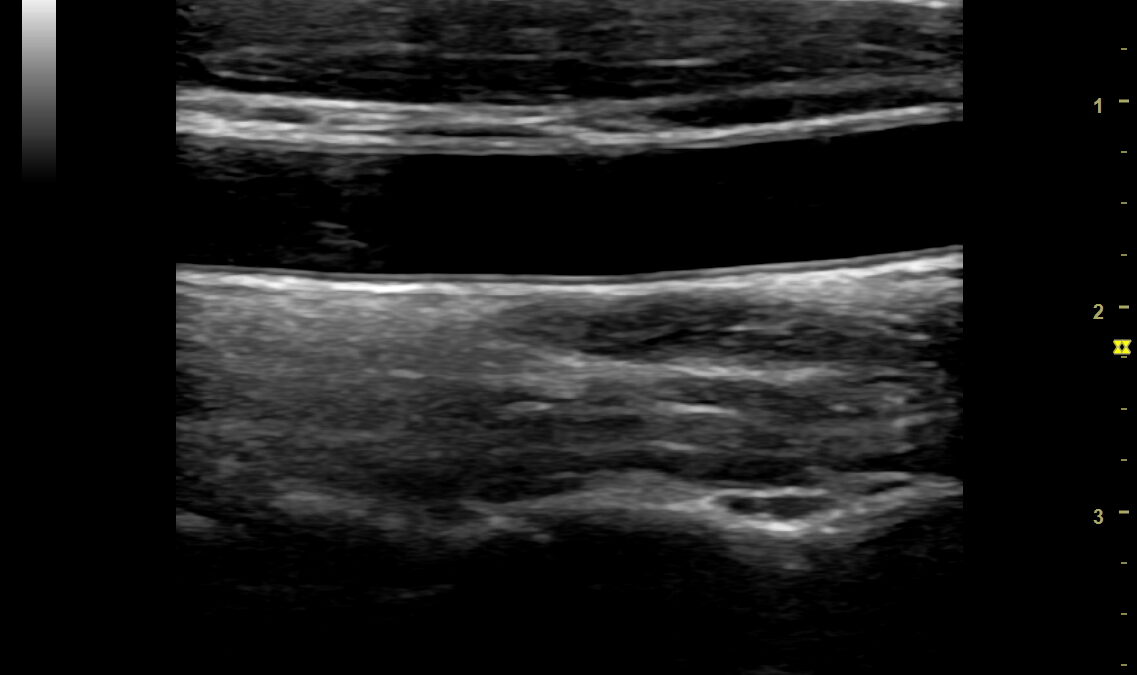

頸動脈は、首の左右を通って脳に血液を送る太い血管です。この頸動脈の壁の厚さや血流を超音波で観察し、動脈硬化の進行度や血管の状態を確認するのが頸動脈エコー検査です。

- 血管壁の厚さ(IMT:内中膜複合体厚) – 厚みが増すと動脈硬化が進んでいるサイン

- プラーク(血管内の脂肪沈着) – 脳梗塞や心筋梗塞の直接原因となることも

- 血流の速度・乱れ – 狭窄や閉塞の有無を確認

- 専用のジェルを塗り、超音波プローブを当てて観察します。

- 画像を解析し、血管壁の厚みやプラークの有無を評価します。

痛みはなく、リラックスして受けられます。結果は画像で確認でき、血管の“老化度”を視覚的に理解できます。

頸動脈エコーで血管壁の厚み(IMT)が増していたり、プラークが確認された場合、それは「血管が年齢より老化している」サインです。つまり、今の生活習慣を見直す“チャンス”でもあります。